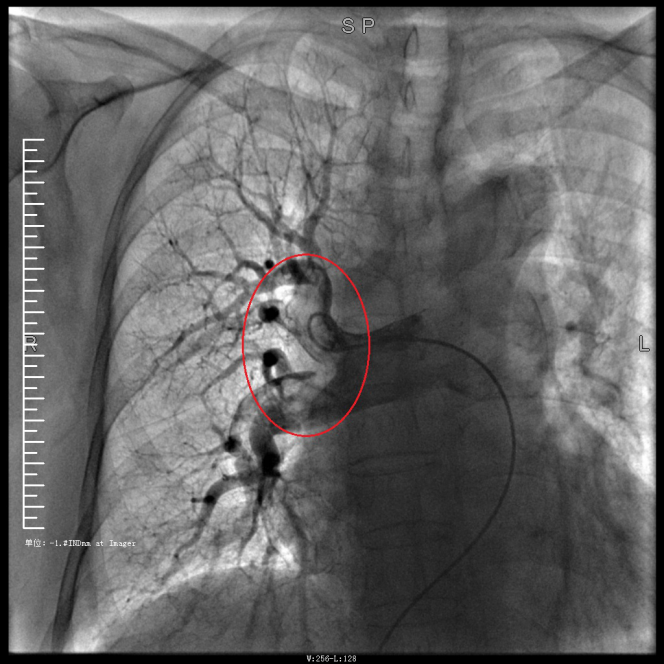

譚婆婆今年已經(jīng)72歲了,因“突發(fā)意識障礙2次”到璧山區(qū)人民醫(yī)院神經(jīng)內科治療。譚婆婆沒有基礎心臟病病史,但近段時間活動耐量明顯下降,稍做活動就出現(xiàn)呼吸困難。入院后查BNP及心臟彩超均未提示明顯異常,查D二聚體明顯升高,經(jīng)心血管內科周波醫(yī)師會診后轉入科室繼續(xù)治療。在心血管內科主任、內科學(心血管病)博士于長青的指導下,周波醫(yī)師成功完成醫(yī)院首例“一站式”微創(chuàng)介入手術。在影像中,可以清晰地看到堵塞的血管經(jīng)溶栓治療后,重新暢通無阻,流動起支撐生命的血液。

肺動脈造影技術是目前診斷肺動脈栓塞的“金標準”,在全程心電監(jiān)護下,通過股靜脈或者頸內靜脈置入鞘管后,利用導絲引導,將造影導管送入肺動脈;可在左/右肺動脈主干及其左右分支內,分別進行肺動脈造影或選擇性肺動脈造影,存在栓塞的肺動脈血管在造影劑注入后即會顯示出充盈缺損、充盈緩慢、或者血管顯影模糊,嚴重栓塞的肺動脈血管甚至會出現(xiàn)血流截斷征象。

肺動脈導管局部置管溶栓術是通過肺動脈造影確定堵塞的肺動脈部位,然后導管尖端置于血栓處,將尿激酶、鏈激酶或重組組織型纖維蛋白溶酶原激活劑直接注入血栓處,新鮮血栓在足量的溶栓劑作用下溶解。肺動脈內局部用藥特別是小劑量時可減少出血并發(fā)癥。

注明:第一張、第二張為術前圖像